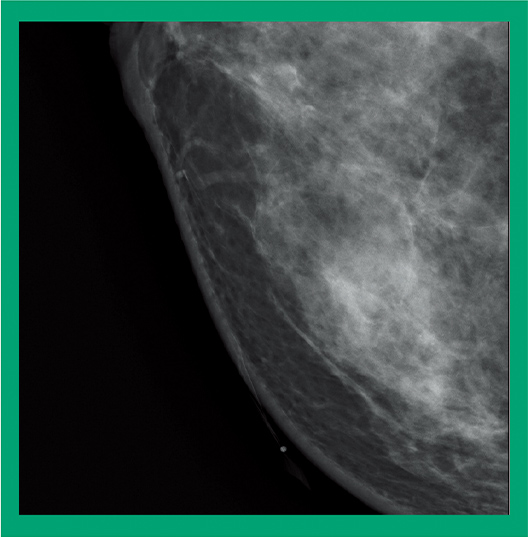

29kV 44mAs 0.83mGy

34mm 62.8N